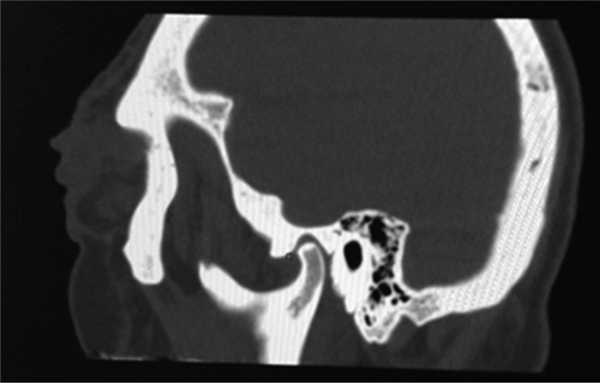

Из анамнеза: перенес холецистэктомию в 2011 г., наблюдался в поликлинике по поводу ишемической болезни сердца, атеросклероза аорты и коронарных артерий, гипертонической болезни I стадии; аллергологический анамнез без особенностей, наследственность не отягощена. Больным себя считает с марта 2014 г., когда по поводу нарастающей слабости, периодического повышения температуры тела и артериального давления (АД) до 170/100 мм рт.ст. обратился в поликлинику по месту жительства. При компьютерной томографии (КТ) органов брюшной полости и забрюшинного пространства и органов малого таза с внутривенным контрастным усилением омнипаком 350—100 мл выявлены признаки каликопиелоэктазии обеих почек (более выражено справа), инфильтративные изменения стенок лоханок в верхней трети обоих мочеточников, выраженные инфильтративные изменения паранефральной клетчатки с обеих сторон, лимфаденопатия брыжейки тонкой кишки с перифокальной инфильтрацией клетчатки. В легких патологических изменений не выявлено. С диагнозом: болезнь Ормонда наблюдался у уролога и получал терапию 20—30 мг преднизолона. При лабораторном обследовании выявлялась умеренная воспалительная активность: л. (11—15)·10 9 /л; СОЭ 36—68 мм/ч, α 1 -глобулины 7,4% (норма 2,3—6,4%), С-реактивный белок 15,1—35,6 г/л; незначительная гипергаммаглобулинемия до 20% (норма 11—18%) в отсутствие в крови ревматоидного фактора (РФ) и онкомаркеров (ПСА, СА-19—9 и РЭА). Заболевание протекало волнообразно, но в январе 2015 г. у больного появился отек век и стал нарастать экзофтальм. Больной направлен на консультацию в НИИР. При осмотре: кожа век пигментирована. На веках ксантелазмы различной величины (см. рис. 1). Лагофтальм 3 мм справа и 4 мм слева. Ограничение подвижности глазных яблок во всех отведениях. Конъюнктива век, переходных и полулунных складок отечны. Складка бульбарной конъюнктивы вдоль всего края нижнего века с двух сторон. Слезный ручей невысокий, ток слезы замедлен. Пальпебральные доли слезных желез увеличены в размерах, отечны, сосуды резко расширены. Другие органы без особенностей. При ультразвуковом исследовании (УЗИ) щитовидной железы выявлены диффузные изменения по типу хронического тиреоидита. Уровни гормонов щитовидной железы в пределах нормы, антитела к тиреоглобулину и тиреоидной пероксидазе не выявлялись. По данным магнитно-резонансной томографии головного мозга и глазниц, картина выраженного двустороннего экзофтальма, который может соответствовать периневральной форме идиопатического псевдотумора глазничной клетчатки с воспалительно-отечными (реактивными?) изменениями слезных желез и мышц глазниц. Исследование с использованием ядерного магнитного резонанса головы выявило единичные мелкие очаги в белом веществе головного мозга, вероятно, сосудистого генеза. КТ брюшной полости и забрюшинного пространства. В полости перикарда определяется незначительное количество жидкости, шириной в области переднего листка до 0,7 см. Печень умеренно увеличена в размерах, структура и плотность ее не изменены. Отмечаются выраженное уплотнение и тяжистость паранефральной клетчатки, обе почечные ножки на этом фоне дифференцируются нечетко. На уровне L II —L IV аорта муфтообразно окружена мягкоткаными структурами, толщина которых достигает 1,2 см. Подобного характера изменения определяются и в области нисходящей аорты на уровне T IX —T X . Кпереди от тел нижнегрудных позвонков визуализируется стелящийся инфильтрат толщиной до 1,3 см. В брыжейке тонкой кишки множество увеличенных до 1,8×1,6 см ЛУ без четких контуров. Компьютерно-томографическая картина не противоречит болезни Ормонда. При сравнении с данными от 2014 г. имеется выраженная отрицательная динамика в виде прогрессирования склеротических изменений и явлений гидронефроза с обеих сторон (больше справа), со значительным замедлением экскреторной функции почек. Для исключения лимфопролиферативного процесса целесообразно дополнительное обследование. При УЗИ глаза и глазницы выявлены признаки выраженного отека век и экзофтальма, значительное увеличение размеров изображения, так называемого стандартного плоскостного ультразвукового среза слезных желез «по глубине и ширине» (OD 2,27×1,52 см; OS 2,23×1,03 см). С обеих сторон имеется неравномерное значительное увеличение толщины прямых глазодвигательных мышц, больше с правой стороны (OD 0,52×0,56 cм; OS 0,48×0,53 см). С правой и левой стороны, между зрительным нервом и прямыми глазодвигательными мышцами, имеются области разряжения, которые особенно хорошо видны с внутренней стороны. При иммунологическом исследовании: высокочувствительный (вч) СРБ 105 мг/л (норма 65 г/л), значительное повышение уровня вчСРБ 181,5 мг/л (норма 5 г/л). Выполнено иммуногистохимическое исследование (ИГХИ) биоптата с использованием антител CD138, IgG, IgG4, panCK, CD20, CD3, CD68 (PGM-1). Полиморфно-клеточный инфильтрат представлен множеством гистиоцитов, СD68 + с примесью лимфоцитов, большая часть которых является Т-лимфоцитами, CD3 + . В-лимфоциты в виде отдельно расположенных небольших групп клеток CD20 + . Плазматические клетки CD138 + в большом количестве, большая часть которых является позитивными по IgG плазмоцитами. При реакции с IgG4 позитивны лишь единичные клетки, составляющие менее 10% позитивных клеток по IgG (что можно объяснить, вероятно, предшествующей терапией стероидами). Заключение: учитывая данные анамнеза и морфологическую картину, следует предполагать заболевание, ассоциированное с IgG4. Исследование, выполненное на проточном цитофлуориметре, выявило увеличение процентного и абсолютного количества Т-клеток (CD3 + 89,3%; 2,2·10 9 /л), Т-цитотоксических клеток (CD3 + CD8 + 44,8%; 1,0·10 9 /л), снижение процентного и абсолютного количества В-клеток (CD19 + CD3 – 0,3%; 0,008·10 9 /л). С учетом неэффективности ранее проводимой терапии глюкокортикостероидами (ГКС) больному начата комбинированная терапия ритуксимабом и эндоксаном, которая является оптимальным лечением при IgG4-CCЗ [29—31]. Внутривенно капельно с премедикацией 500 мг солюмедрола введены 1000 мг ритуксимаба и 1000 мг эндоксана 1 раз в 2 нед (2 вливания на курс) с последующим введением эндоксана 1 раз в 14 дней (4 на курс) и поддерживающей терапии метилпреднизолоном 4 мг. При оценке эффективности терапии через 4 мес объективно сохранялся выраженный экзофтальм, периодически отмечался подъем температуры до фебрильной. При лабораторном исследовании отмечено снижение показателей воспалительной активности (Hb 136 г/л, л. 11,5·10 9 /л, тр. 433·10 9 /л, СОЭ 50 мм/ч по Вестегрену (норма до 20 мм/ч), вчСРБ 15,2 мг/л, снижение уровня IgG4 до 2,1 г/л. Наблюдалось полное истощение B-клеток CD19 + в крови. При мультиспиральной КТ (МСКТ) глазниц после внутривенного введения 100 мл визипака в отсроченную фазу в ретробульбарной клетчатке определяется мягкотканое образование с неровными контурами, полностью выполняющее полости глазниц, гомогенной структуры, размерами справа 3,3×4,3×3,5 см, слева 3,3×3,7×3,6 см. Мышцы глаз, слезные железы на этом фоне нечетко дифференцируются. Зрительные нервы окружены мягкоткаными разрастаниями, истончены. Определяется двусторонний экзофтальм. Костно-деструктивных изменений нет. Выполнена МСКТ органов брюшной полости после контрастирования желудочно-кишечного тракта до и после введения везипака. Заключение: проявление ретроперитонеального фиброза. Умеренная двусторонняя пиелоэктазия. Умеренная гепатомегалия. Состояние после холецистэктомии. Незначительный перикардит. Множественные увеличенные ЛУ брыжейки тонкой кишки. При сравнении с данными КТ от 2015 г. без динамики. С учетом прогрессирования клинических проявлений псевдотумора глазниц (см. рис. 2, рис. 3), отсутствия положительной динамики при МСКТ глазниц и органов брюшной полости на фоне терапии, некоторых необычных клинических (периодические подъемы температуры до фебрильной, наличие множественных ксантелазм век) и морфологических (наличие большого количества гистиоцитов и недостаточного количество плазмоцитов, секретирующих IgG4, при ИГХИ для постановки диагноза IgG4-ССЗ) проявлений решено провести дополнительное обследование больного с пересмотром биоптатов для исключения системного варианта гистиоцитоза. Проведена позитронно-эмиссионная томография (ПЭТ) для исключения генерализованного гистиоцитоза. Заключение: данных о наличии агрессивного лимфопролиферативного заболевания, а также другого неопластического процесса не получено. Псевдотумор глазниц, генерализованный фиброз медиастинальный, внутрибрюшной, внутритазовый и забрюшиной клетчатки с минимальным воспалительным компонентом. Изменения по типу «волосатой почки» и «облицованной аорты». Внутрибрюшная лимфоаденопатия, вероятнее всего, реактивного генеза. Двусторонний пневмофиброз, застойные (?) изменения в базальных отделах легких. Двусторонний гидронефроз. Гепатомегалия. Генерализованная мелкоячеистая перестройка костей скелета (остеопороз?). Накопление препарата в скелете, вероятнее всего, за счет раздражения костного мозга (см. рис. 4). При К.Т. нижних конечностей и костей черепа выявлены множественные остеосклеротические изменения в дистальных отделах бедренных и большеберцовых костей (рис. 5) и плоских костях черепа (рис. 6). Сцинтиграфия костей: выявлены множественные склеротические перестройки костного мозга. Симметричная патологическое избыточное накопление радиофармпрепарата (РФП) в костях лицевого скелета, эпифизах, метафизах и метадиафизах трубчатых костей наиболее выраженное в бедренных, большеберцовых и костях стоп. Повышенное накопление в чашечно-лоханочной системе правой почки. Однофотонная эмиссионная КТ/КТ черепа и коленных суставов: очаги патологического избыточного накопления РФП соответствуют склеротической перестройке костного мозга. Пересмотр гистологических препаратов с ИГХИ: среди полиморфно-клеточного инфильтрата большое количество гистиоцитов, пенистых клеток, скопления плазматических клеток. Гистиоциты СD68 + , S100 – , IgG4 + , единичные плазматические клетки. Субстрат поражения может принадлежать гистиоцитозу, учитывая локализацию следует предполагать БЭЧ (см. рис. 7). Методом полимеразной цепной реакции в реальном времени с анализом кривых плавления (Rotor Gene 6000) выполнено молекулярное исследование биоптатов. В 599—601-м кодонах 15-го экзона гена BRAF мутация не обнаружена. На рис. 8 представлена частота повторяющихся клинико-радиологических находок у больных БЭЧ, согласно данным литературы и в нашем случае заболевания. Таким образом, больному диагностирован генерализованный гистиоцитоз: БЭЧ с конституциональными нарушениями (лихорадка, патологическая утомляемость, снижение массы тела), поражением кожи и области глазниц (ксантелазмы век, экзофтальм, псевдотумор глазниц, дакриоаденит), костей (остеосклеротические поражения бедренных, малоберцовых и плоских костей черепа), поражение сердечно-сосудистой системы (выпотной перикардит, поражение грудной и брюшной аорты по типу «облицованной аорты»), ретроперитонеальных проявлений (гидронефроз, пиелоэктазия за счет инфильтрации околопочечной ткани по типу «волосатой почки») c отрицательной мутацией BRAFV600E.

Рис. 6. Остеосклеротические очаги в плоских костях черепа.